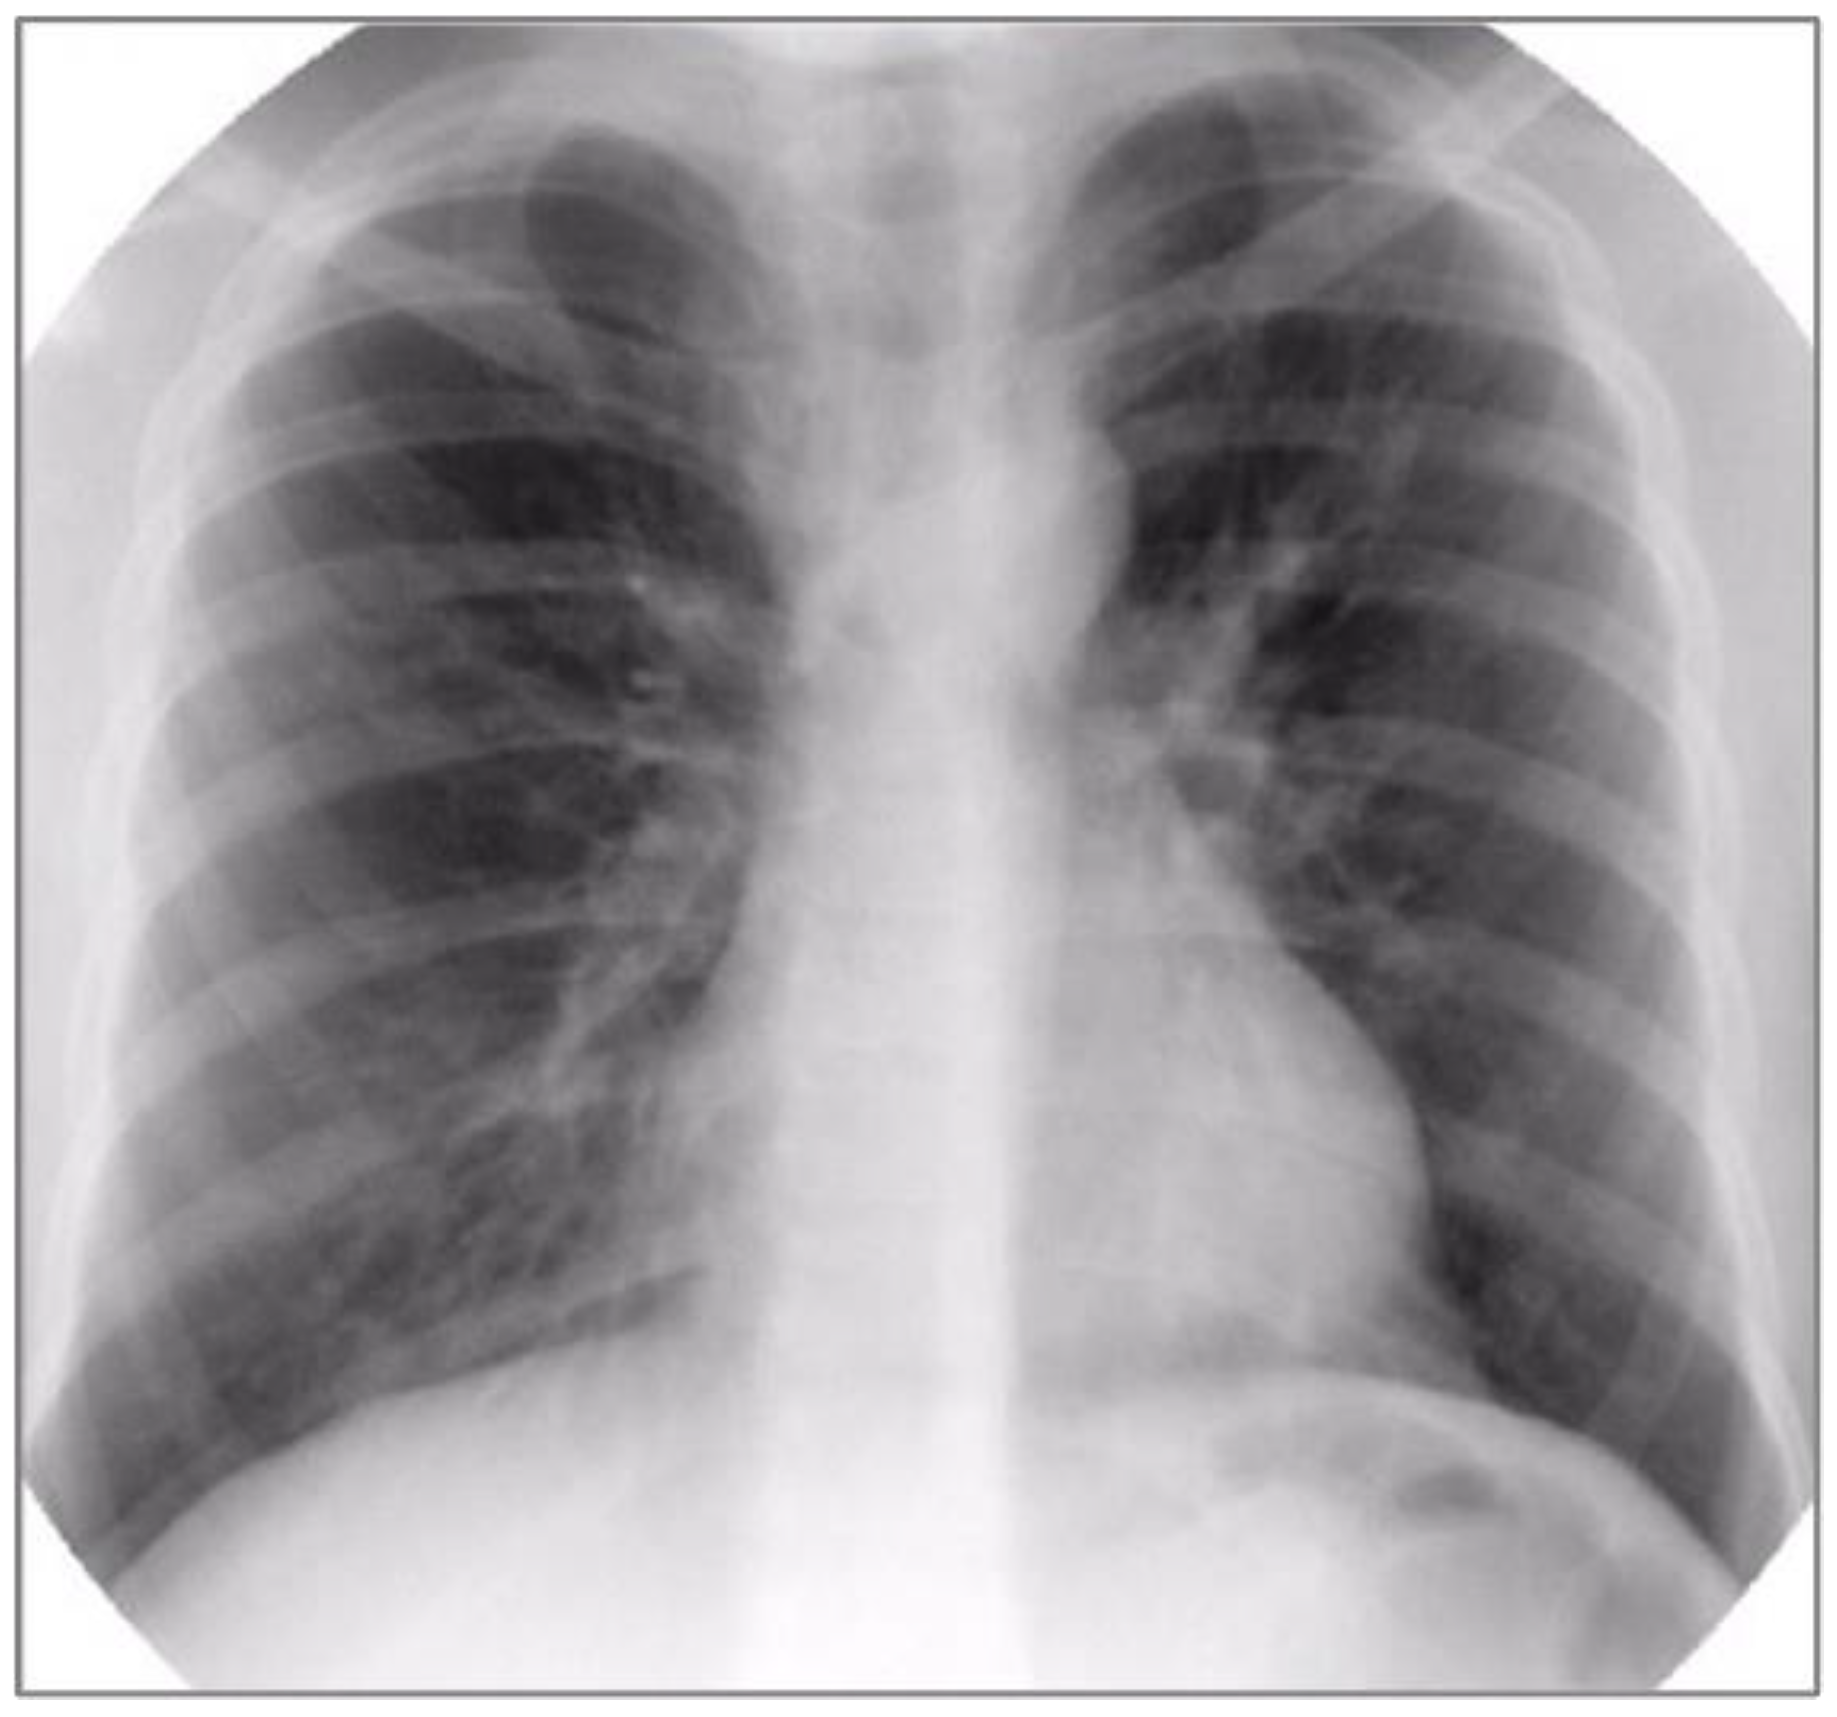

3. Case Report